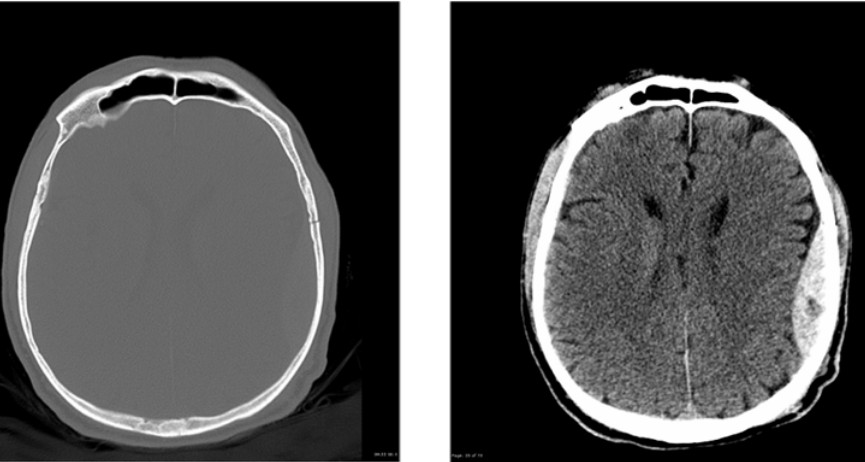

Epidural haematoma with rural deterioration

A previously well 35-year-old man presents to a rural ED 90 km from the nearest trauma centre following an isolated …